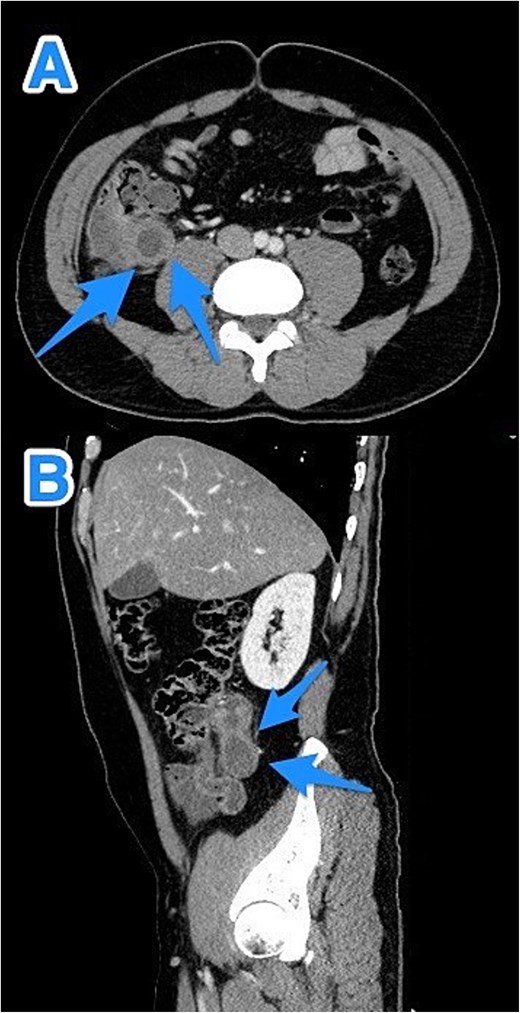

A 46-year-old male, with no previous medical or surgical history, presented to the emergency department with a 4-day history of right lower abdominal pain, which initially originated in the epigastric region before migrating to the right iliac fossa. It was constant, progressive, and not relieved by simple analgesics. The patient reported associated nausea and anorexia but denied any history of fever or vomiting. On physical examination, the patient was vitally stable, alert, conscious, and in moderate pain. There was rebound tenderness in the RLQ, and the remainder of abdomen was soft, with no other positive findings. Laboratory investigations were within normal ranges. Contrast-enhanced CT imaging of the abdomen and pelvis detected a dilated, blind-ended tubular structure in the right lower quadrant, with thick fluid content and incomplete calcifications along its circumference. A focal area of wall discontinuity with thick fluid collection in the right paracolic gutter and pelvis was observed (Fig. 3). Additionally, small ascites with thickened and enhancing peritoneal reflections were noted. The diagnosis of a ruptured appendiceal mucocele was made. A right hemicolectomy was performed, and the patient's postoperative course remained stable and uneventful.

CT abdomen and pelvis with contrast: (A) coronal, (B) axial, and (C) sagittal views demonstrate a dilated, blind-ended structure in the right lower quadrant with incomplete circumferential calcifications and thick fluid content, consistent with an appendiceal mucocele (arrows).